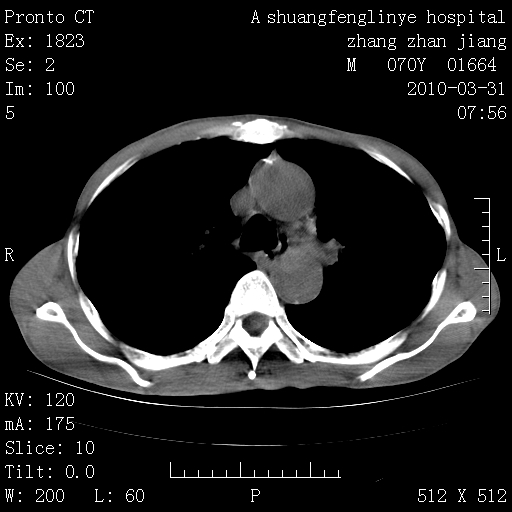

双上肺继发型tb并左上空洞形成,主动脉冠脉钙化。

支持:继发性肺结核伴空洞形成!建议纤支镜检查待出外周围型肺癌可能!

1)两肺上叶继发性肺结核并左肺上叶空洞形成。2)冠状动脉及主动脉钙化。